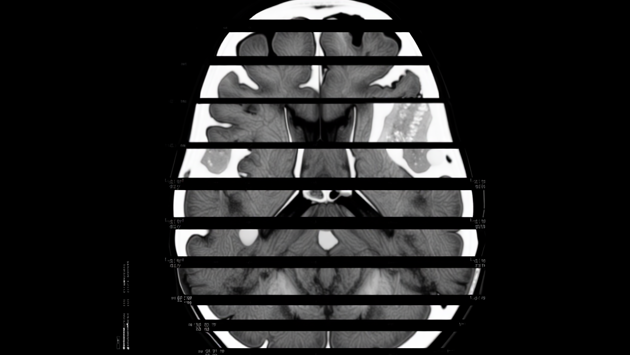

С 2021 года компания внедряет медицинскую платформу, а в 2024 году получила регистрационное удостоверение Министерства здравоохранения РФ на собственное программное обеспечение, признанное медицинским изделием. Система искусственного интеллекта используется для анализа КТ-снимков мозга и уже внедрена в 12 регионах страны.

Текущая версия ИИ успешно определяет признаки инсульта и рассеянного склероза. По словам Паламарчука, на финальной стадии готовности находится модуль, позволяющий выявлять деменцию и болезнь Альцгеймера на раннем этапе.

Кроме того, компания разрабатывает технологию, которая позволит на основе анализа состояния мозга прогнозировать развитие неврологических заболеваний. Сейчас это решение находится в процессе государственной регистрации, пишет Газета.Ru.